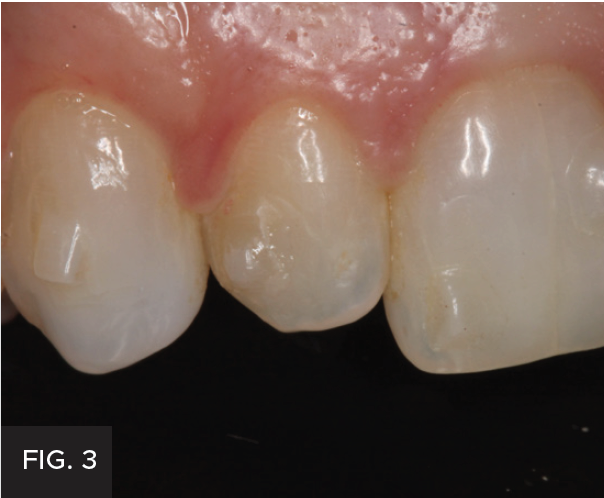

After the patient’s crowding issues had been corrected with orthodontics, the gingival display at #7 was excellent. All that remained was to restore the tooth to proper dimensions. (FIG 3 & 4) Different treatment options were discussed with the patient, including a composite veneer, Class IV restoration, and minimal-preparation porcelain veneer. Each option’s expected longevity was explained. The patient chose to have the tooth restored with a Class IV mesial-incisal-distal restoration.

The pre-operative right 1:1 view shows deep incisal embrasures on tooth #7 and orthodontic composite tabs.